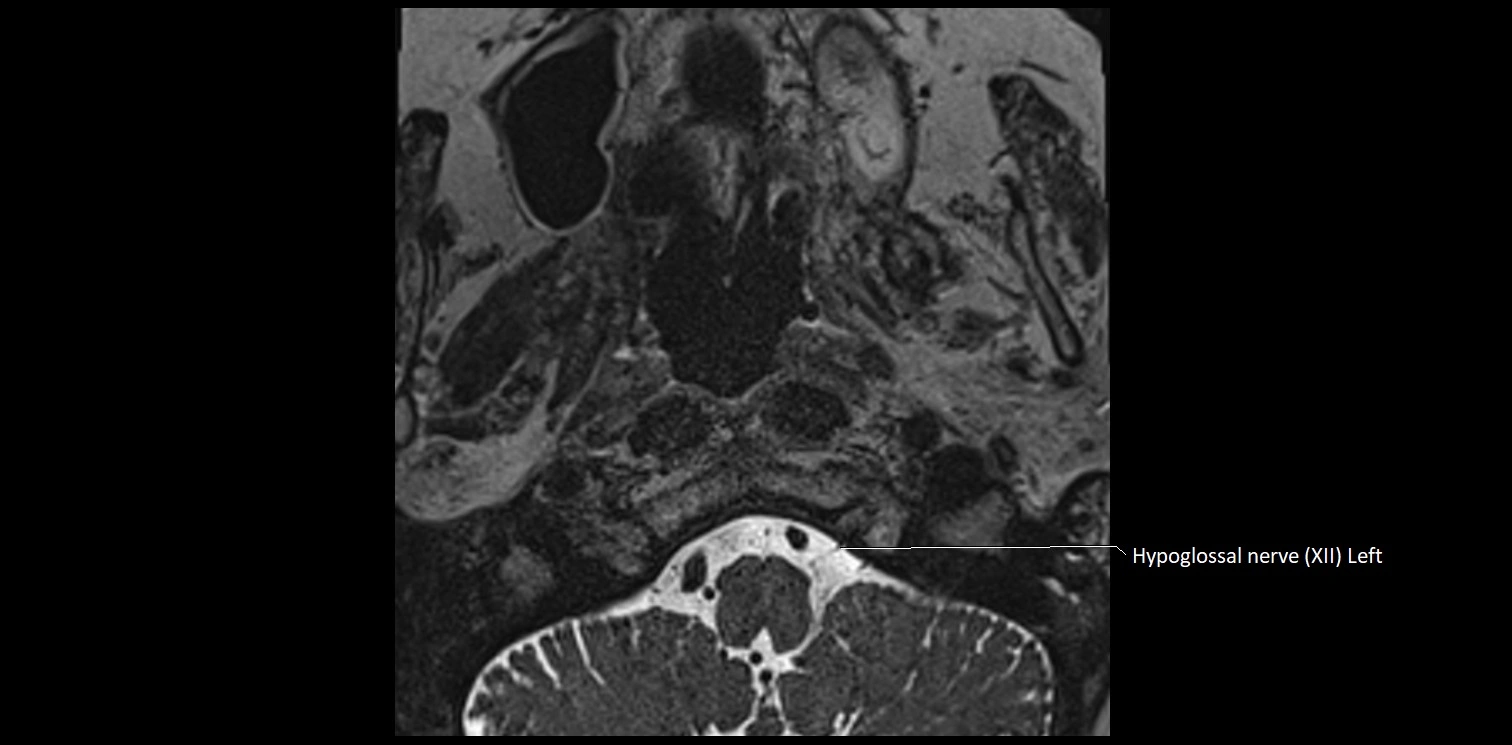

MRI images

image